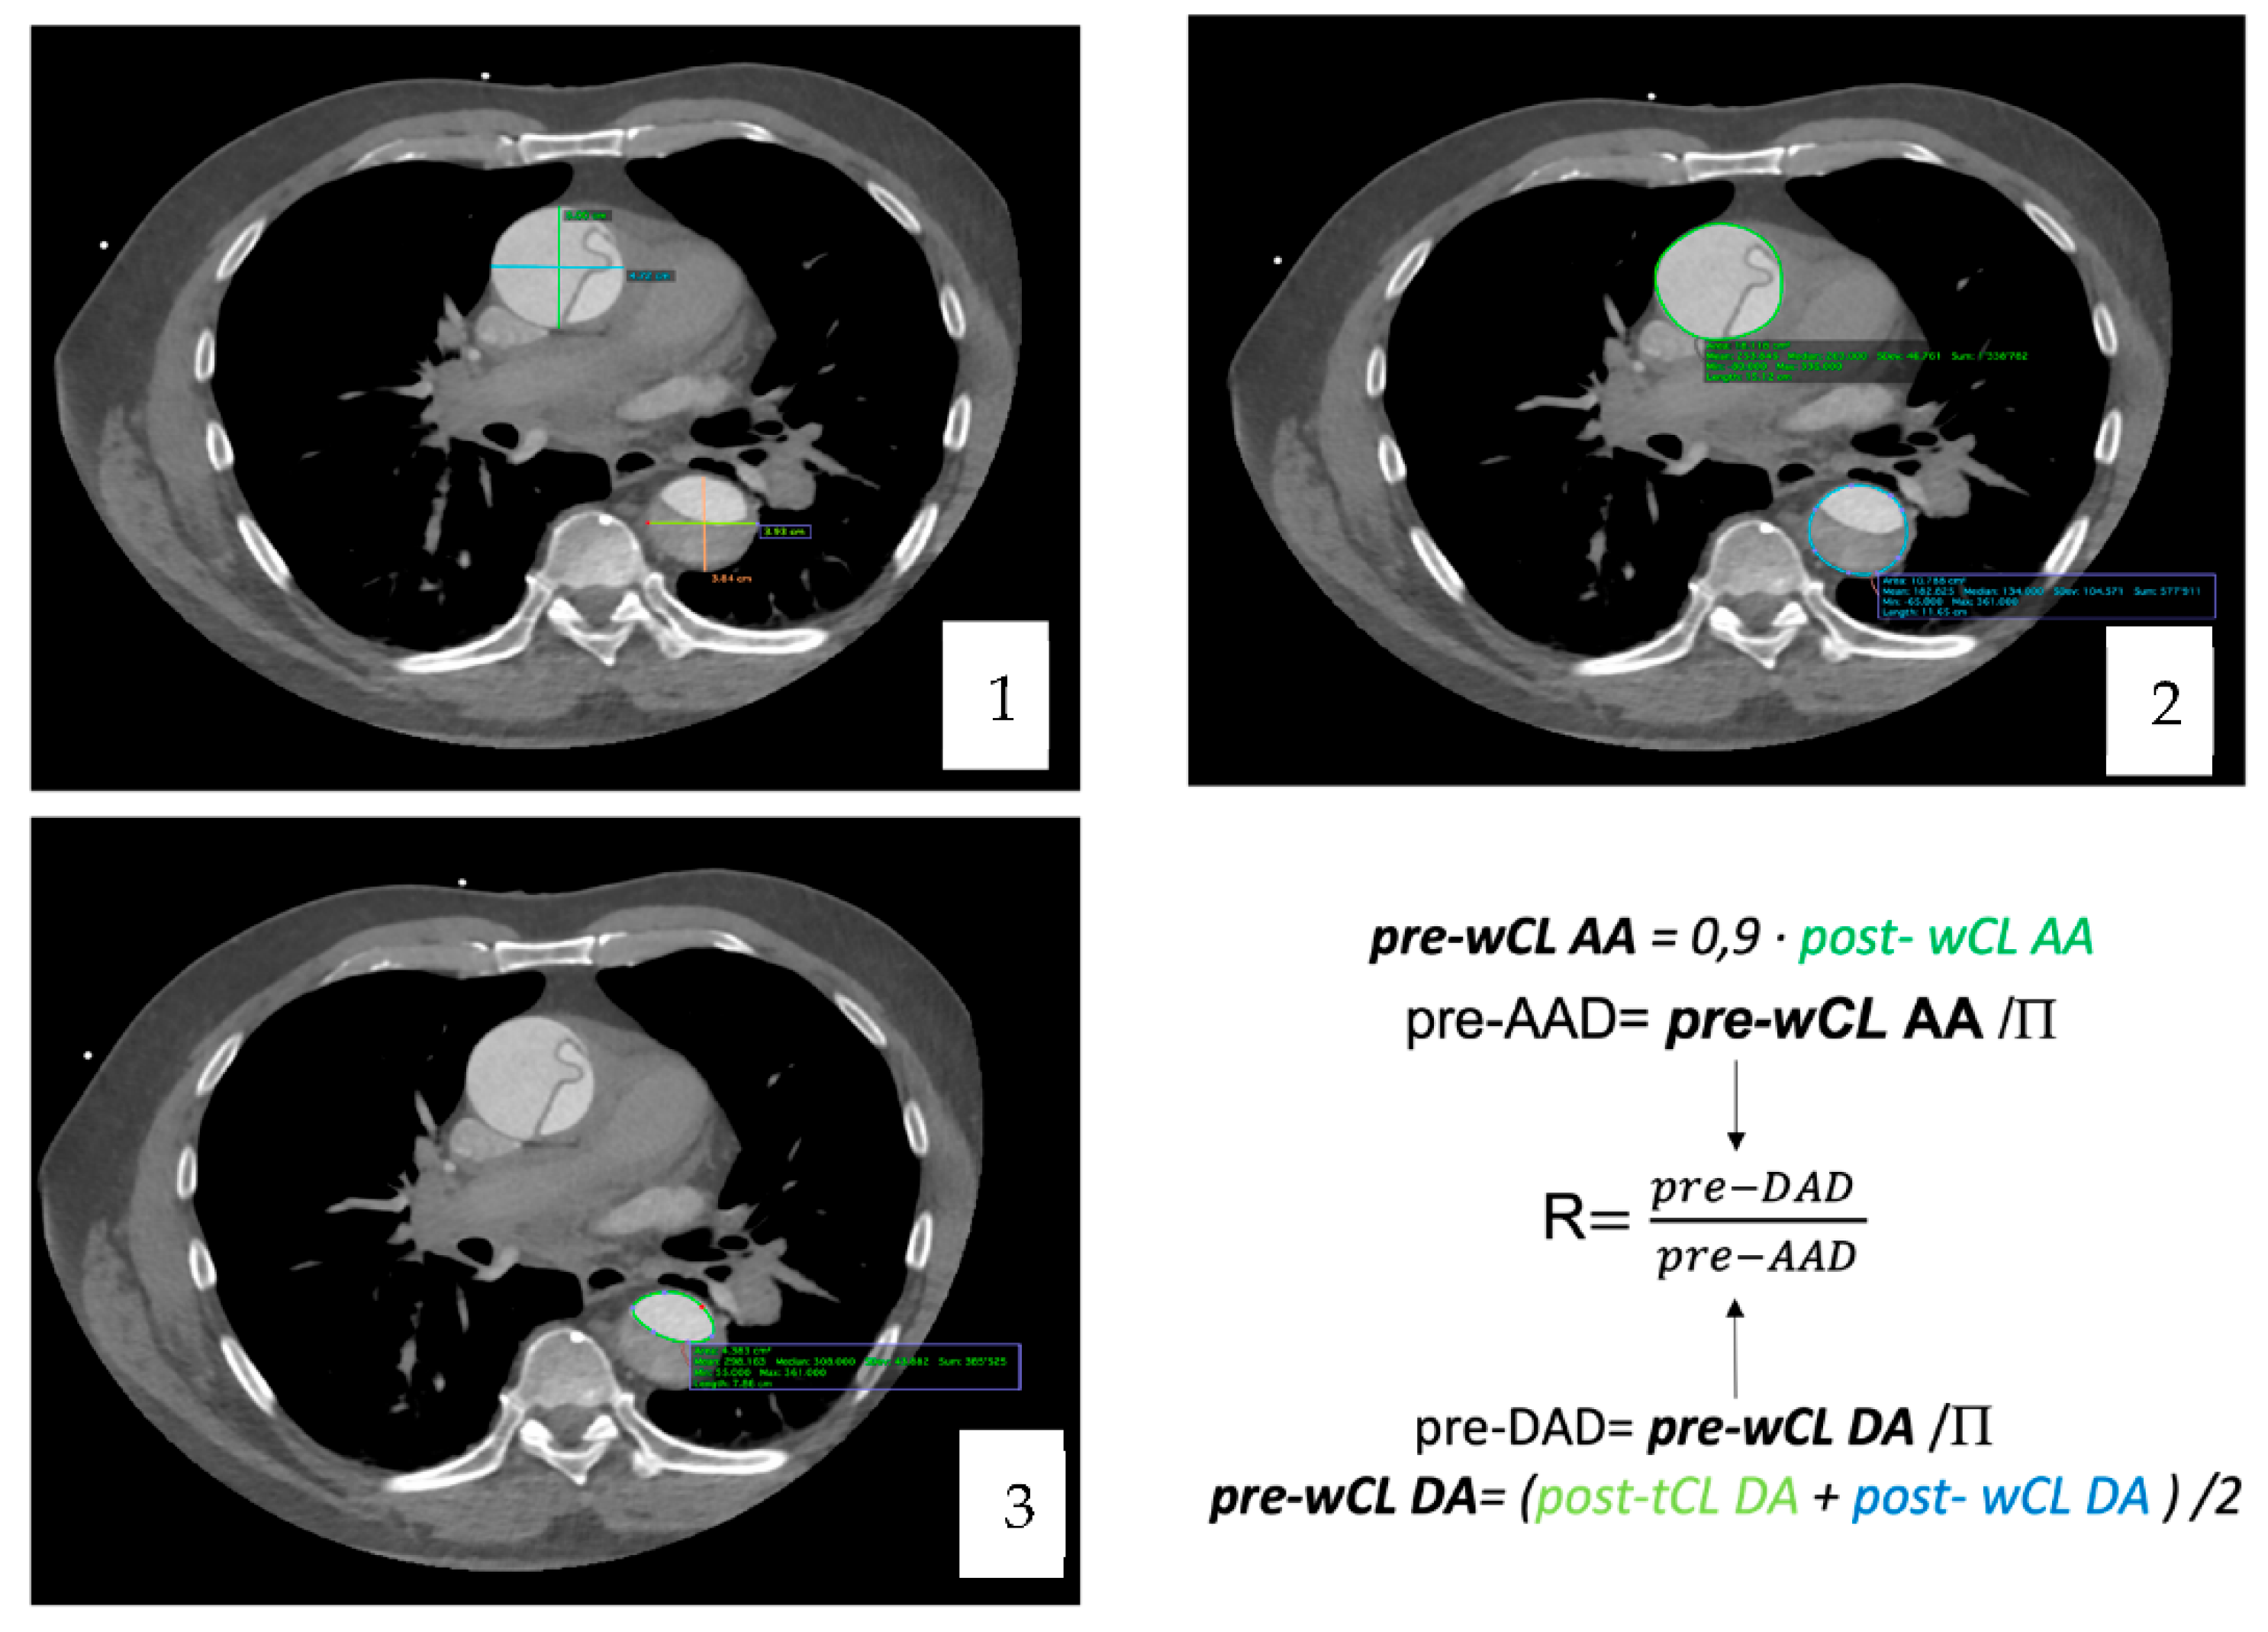

Computer tomography angiography studies were analyzed using the curved multiplane reformats with the DICOM viewer OsiriX vd.12.01. Measures were manually taken, in an orthogonal plan (sagittal, axial and coronal). A reference point to do all the measures was determined at the level of the pulmonary artery bifurcation [Figure 2] [Figure 3].

To calculate the pre-dissected AAD, we extrapolated it from the whole circumference length (wCL) [pre-dissected AAD = pre-dissected wCL/P] which was obtained with the T. Yamauchi et al. equation [10].

[pre-wCL = 0.9 · post-wCL]

As for the descending aorta, the equation applied was the one proposed for clinical use by T. Yamauchi in his article from 2018 [11].

[pre-wCL = (post-tCL + post-wCL)/2].

The diameter was then extrapolated from the perimeter with the equation [pre-DAD = pre-dissected WCL/Π]. Once the maximal pre-dissected AAD and DAD were obtained, the ratio between them was computed.

Figure 3. Imaging process and methodology. (1) Maximal diameters (AP and LL) of AA and DA. (2) AA post-wCL and area and DA post-wCL and area (3) DA post-tCL and area.